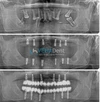

علاج الزرعات السنية (Implant)